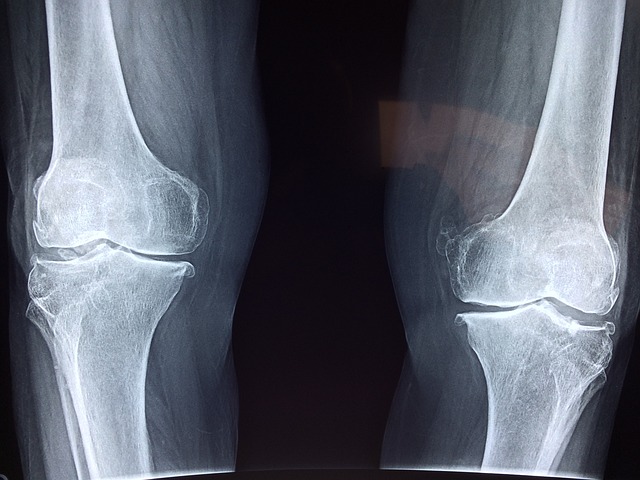

무릎 관절은 우리 몸에서 가장 큰 관절이며, 걷기, 달리기, 앉기, 서기 등 다양한 활동을 수행하는 데 중요한 역할을 합니다. 하지만 무릎은 체중을 지지하고 다양한 움직임을  감당해야 하기 때문에 손상이나 질병에 치약 하기도 합니다. 어느 날 내게 찾아오는 무릎 통증의 원인과 증상, 퇴행성 관절염에서 인대 파열까지 알아보도록 하겠습니다.

●퇴행성 관절염 : 연골이 점차 마모되어 발생하는 관절 질환이며 연골은 뼈 끝을  덮고 쿠션 역할을 하는 부드럽고 흰색의 조직입니다. 연골이 마모되면 뼈가 서로 문질러 통증, 붓기, 뻣뻣함을 유발할 수 있습니다. 관절 주변을 압박하면 통증이 느껴지고 관절안에 물이 차거나 소리가 날 수 있으며, 증상이 심하면 다리가 'O' 자 모양으로 변할 수 있습니다.

4) 퇴행성 변화

무릎 관절의 퇴행성 변화는 나이가 들면서 연골이 점차 마모되고 뼈가 서로 맞닿아 발생하는 질환입니다. 연골은 뼈 끝을 덮고 쿠션 역할을 하는 부드럽고 흰색의 조직입니다. 연골이 마모되면 뼈가 서로 문질러 통증, 붓기, 뻣뻣함을 유발할 수 있습니다.